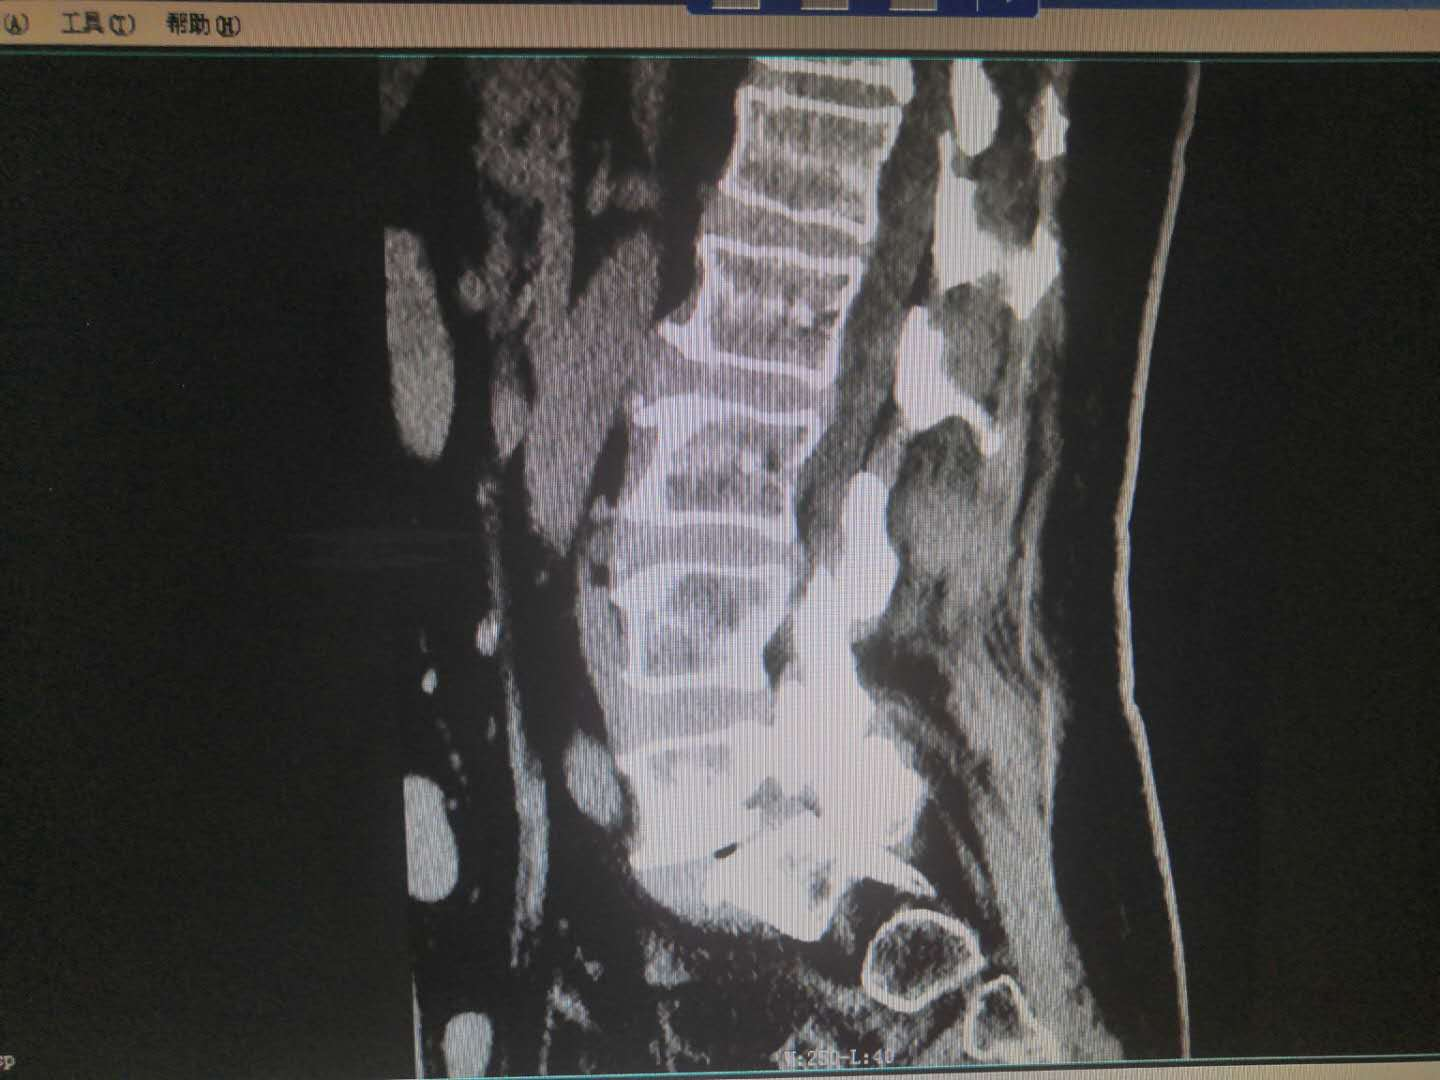

患   者:杨某,女,56岁。

主   诉:因反复腰痛伴右下肢疼痛麻木8年,加重6月,入院治疗。

现病史:缘于8年前开始无明显诱因出现腰部疼痛,呈间歇性胀痛,持续时间数分钟至数小时不等,放射至右下肢,伴右下肢麻木,此后症状反复出现,持续时间数小时至数天不等,劳累后加重,休息后缓解,6月前加重,并出现间歇性跛行,目前行走约200米左右需休息后方能继续行走,在当地医院治疗(药物+理疗)后效果欠佳,现特至我院就诊。

专科检查:颈胸椎各棘突无明显压痛,颈部活动正常,L3-5棘突及椎旁存轻压痛及叩击痛,疼痛无放射,腰部屈伸活动轻度受限,右下肢直腿抬高试验阳性(40度),加强试验阳性,双侧跟臀试验阴性,拾物实验阴性,右侧股四头肌、右足拇背伸肌力约4级,右小腿后、外侧、足背、足底感觉较左侧减退,肢端血运正常。

术前影像资料:

诊       断:

腰椎滑脱症(腰5向前III度)并腰椎管狭窄症。

治疗方案:

入院讨论后予在全麻下行腰4、5、骶1椎弓根螺钉内固定+腰5滑脱复位+腰5/骶1髓核摘除并Cage植入椎间植骨融合术。

术后影像资料:

专家指导

针对此病例诊断及治疗方案,杨述华教授指导如下:

首先此病例手术做的非常好,展示了武冈展辉医院骨科专家精湛的手术技术。

此病例的诊断也很正确,腰椎滑脱需要采取手术治疗进行复位。

此手术一个切口四个手术,需要减压、复位、固定、植骨,植骨是最重要的。近年来临床上不主张百分百复位,此病例若百分百复位,会有一定的症状。